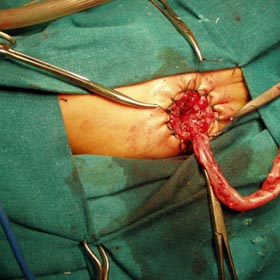

Abdominal Wall Defects

The survival rate of our patients with Omphalocele and Gastroschisis has gradually improved with the latest treatment modalities available in the hospital. My personal goal is to achieve closure of the defect with the lowest morbidity, mortality and shorten the lengthy hospitalization.

Abdominal Wall Defect